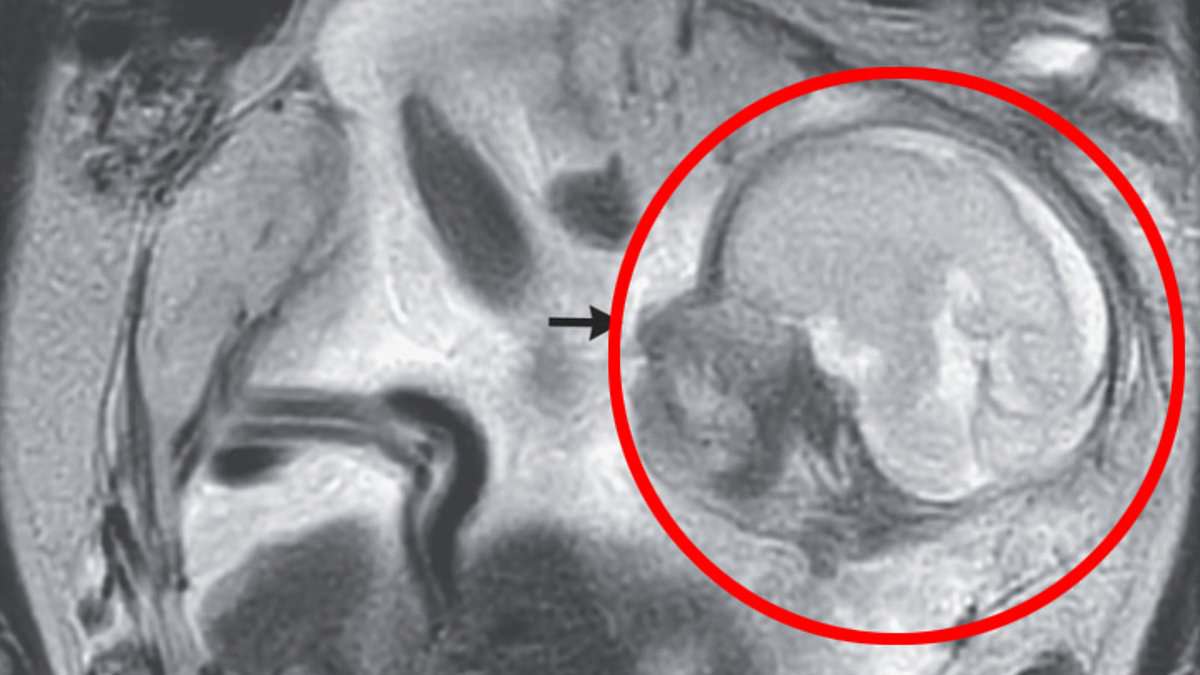

A woman presented at a remote island's emergency room with severe stomach pain and was shocked to learn that she was 23 weeks pregnant, but with an incredibly rare abdominal pregnancy. Doctors discovered a healthy placenta and fetus growing outside her uterus, attached to her abdominal cavity. Recognizing the risks, the woman was transferred to another hospital where she underwent abdominal surgery to safely remove the fetus. Both mother and baby recovered well, and two months later, they were reunited and able to go home. Abdominal pregnancies are extremely rare, occurring in only 1% of ectopic pregnancies.